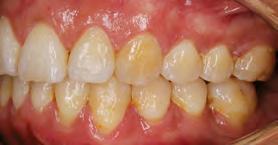

52 | SONRIENDO AL FUTURO

Tratamiento ortodóncico en paciente adulto tratado con extracciones de primeros molares permanentes. Reporte de caso

en paciente adulto tratado con extracciones de primeros molares permanentes. Reporte de caso

Dentista y Paciente 52 Sonriendo al futuro